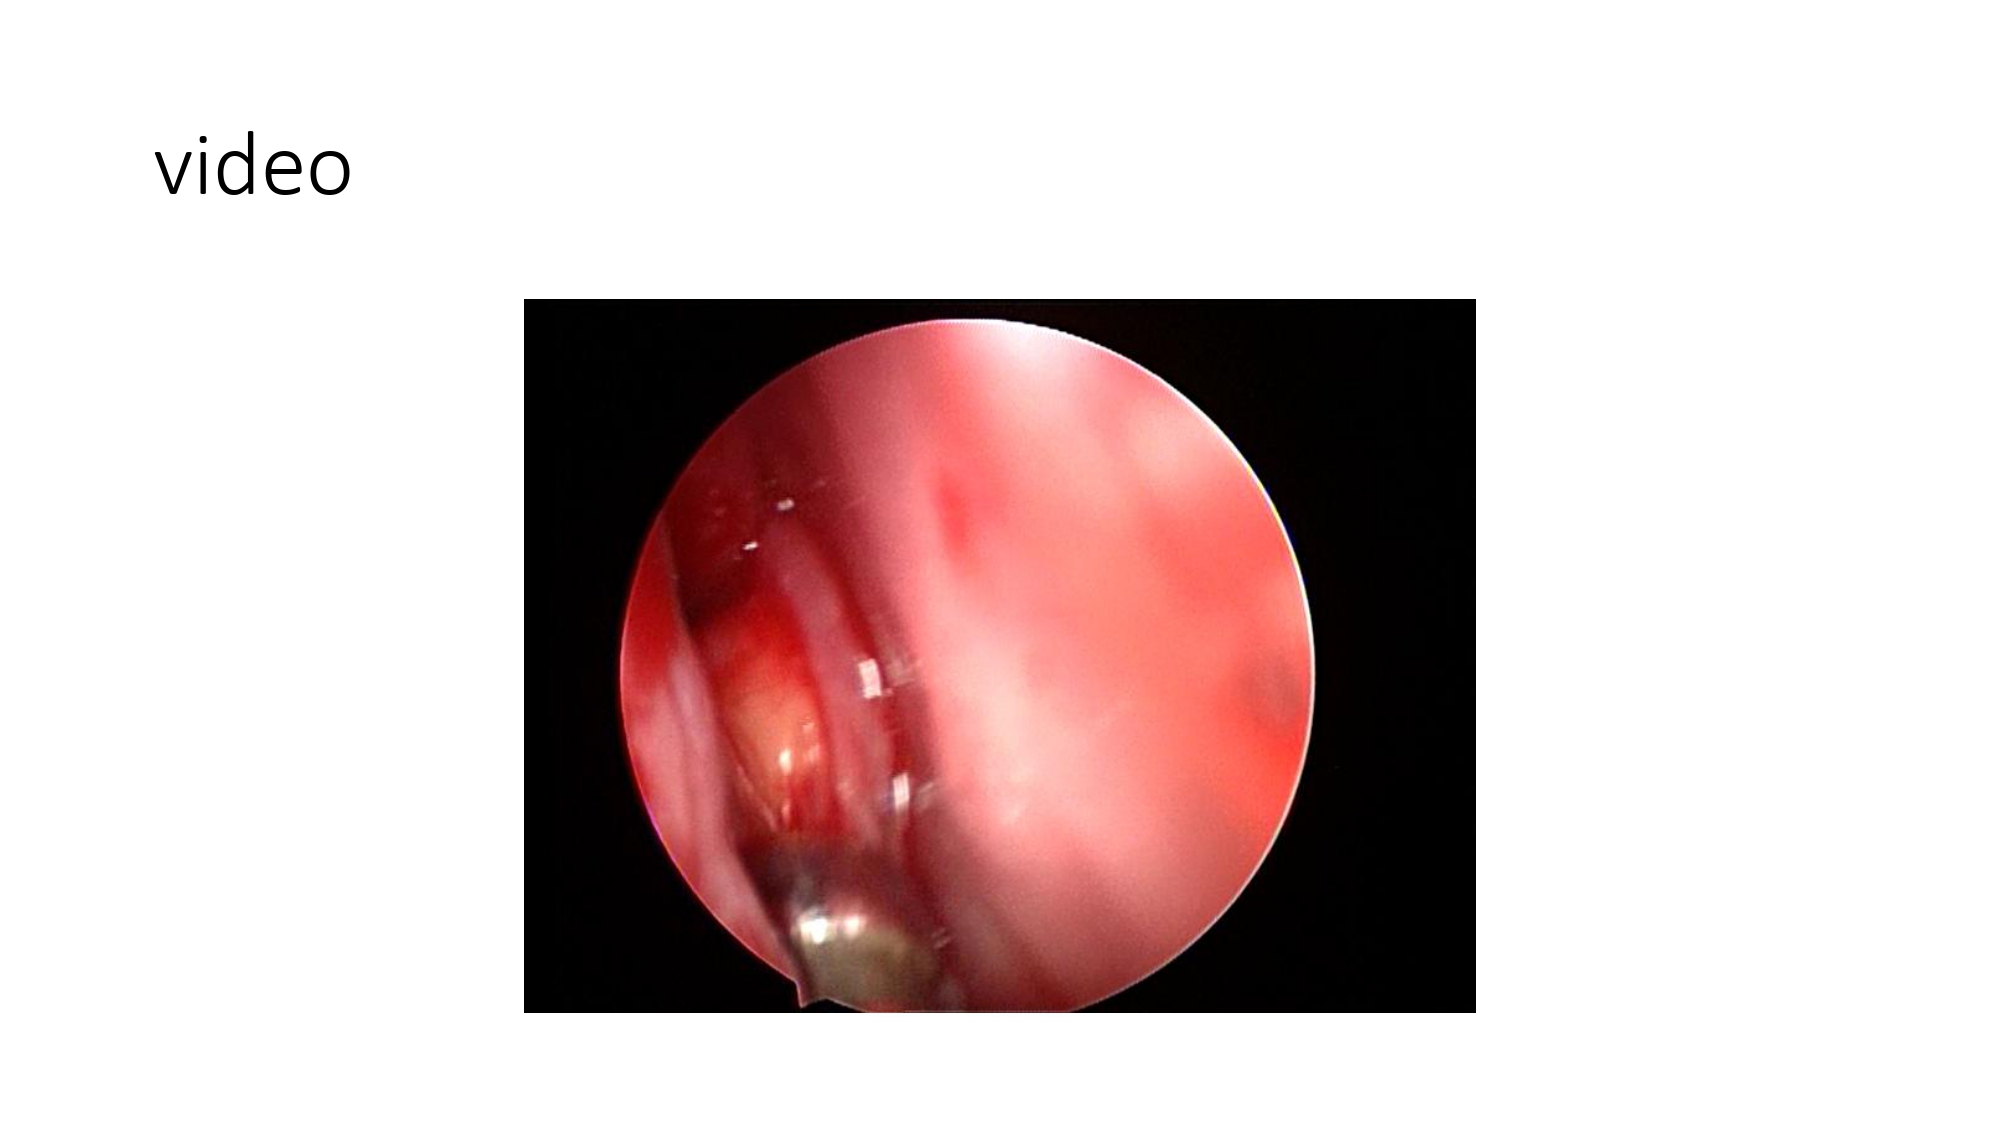

| 15:10 - 16:10 | Interactive Case Demonstration and Discussion II: ~20 minutes each, (5 minutes presentation followed by 15 minutes discussion) Practicals: How I am doing it? Participants present case presentations about how they do it? The faculty comment on and discussion. 1. Endoscopic approach in post-traumatic CSF leakage - Dr. Nguyen Thanh Xuan 2. Endovascular approach in CCF - Assoc. Prof. Le Thanh Dung | Prof. Christian Matula International & local faculties Participants | |